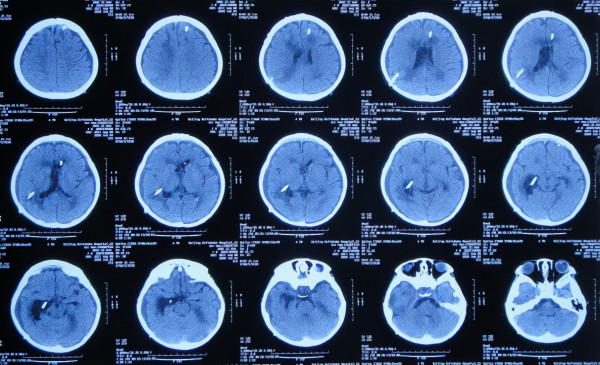

患兒於2019年12月5日下午,出現發熱,家屬自行給予口服布洛芬混懸液治療,但2019年12月6日凌晨2點左右,患兒睡眠中喊頭痛,家屬開車急送至安徽省蕪湖市弋磯山某三甲醫院,去醫院途中病情變重患兒呼之不應;到院後急診查頭部增強CT示蛛網膜下腔出血(圖-1),考慮血管畸形,於凌晨4點急診進行了腦室外引流術;術後當天早晨8點進行了DSA檢查排除血管畸形(圖-2)。

圖-1:2019年12月6日頭部增強CT

腦室外引流術後次日即2019年12月7日,查頭部CT示腦室出血,引流術後狀態(圖-3)。

圖-3:2019年12月7日頭部CT

引流術後3天即2019年12月9日,再次查頭部增強CT掃描示胺區腫瘤(圖-4)。

圖-4:2019年12月9日頭部增強CT